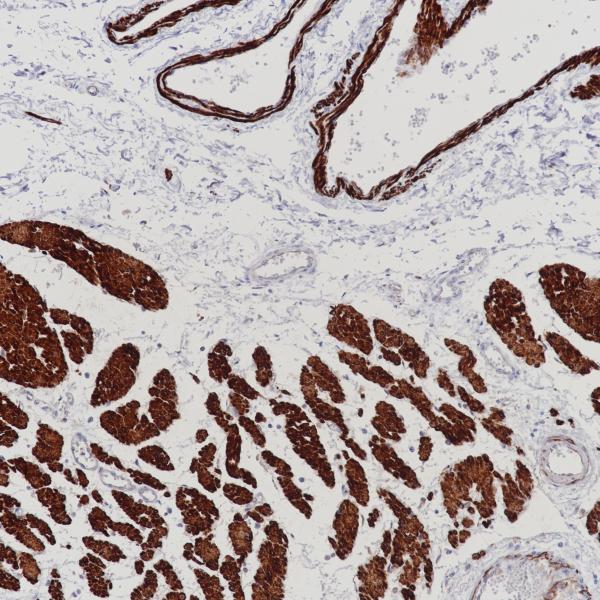

Desmin

D33